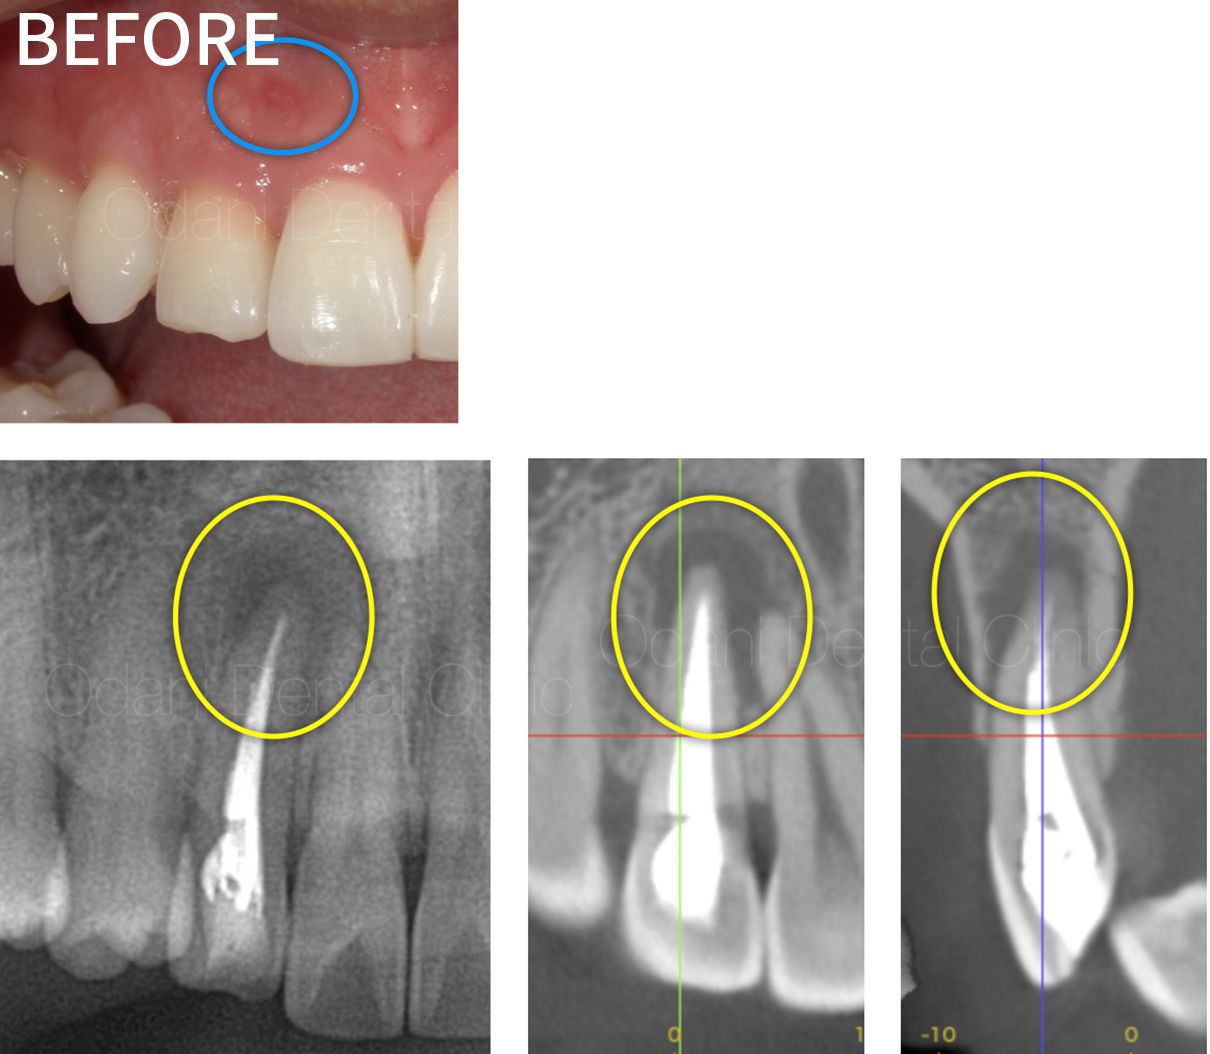

| 主訴 | 右上前歯の根の先の辺りに違和感がある |

|---|---|

| 年齢 | 20代男性 |

| 期間 |

|

| 治療部位 | 右上前歯 |

| 治療内容 |

感染根管治療(再治療) ラバーダム防湿を行い、唾液の侵入のない環境づくりを行った上で、周囲をよく消毒してから、30倍まで拡大できるマイクロスコープ下で、根管内に詰まっていた詰め物や汚れを除去後に清掃・洗浄を丁寧に行いました。洗浄には、薬剤や超音波洗浄に加え、超弾性ニッケルチタンファイルやEr:YAGレーザーも併用し、根管内の細菌除去を徹底し、根管充填(根の中の詰め物)を行いました。 |

| 治療費 |

前歯 感染根管治療(再治療) 7.7万円(税込) ※土台の補強の費用は別途となりますが、前歯の場合は状況によってかぶせ物にしない場合もあります。 |

| 起こりうるリスク |

治療後に一時的な痛みや違和感が出ることがあります。 根の病気が再発する可能性があります。 歯の変色が進んでいく可能性があります。 再発した場合、外科的な根管治療が必要になることがあります。 |